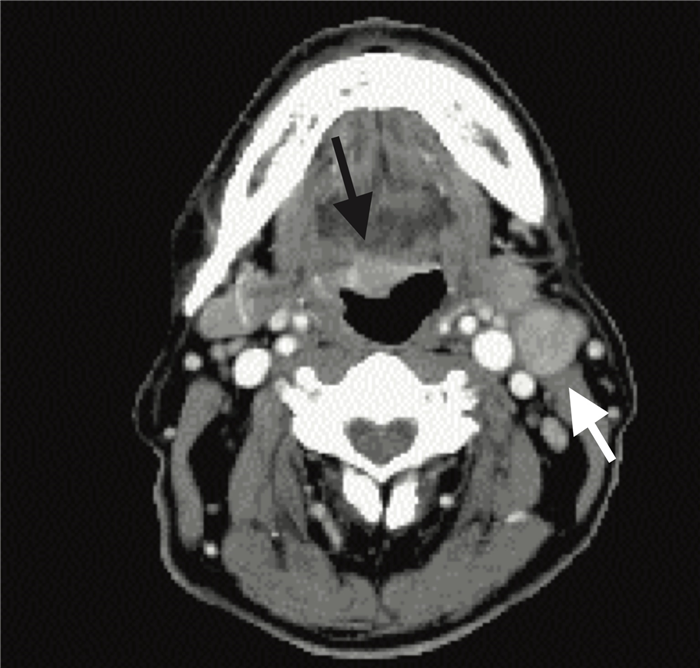

На постконтрастном изображении белой стрелкой указан увеличенный лимфатический узел IV группы. У пациента удалена правая доля щитовидной железы и правая яремная вена, что указано чёрной стрелкой, всвязи с папиллярной карциномой.

На постконтрастном изображении белой стрелкой указан увеличенный лимфатический узел V группы.